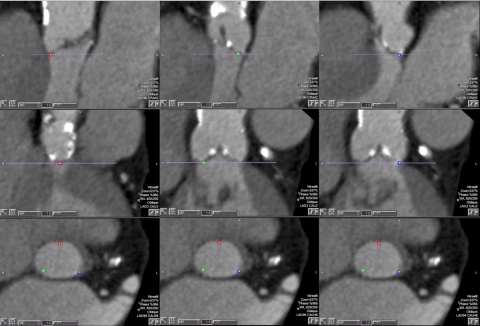

Sehr geehrter Herr Winter,gerne berichte ich über die Erfahrungen mit dem von der Firma Winray gelieferten Röntgencontainer.Als Betreiber einer radiologischen Anlage stellen sich in der…